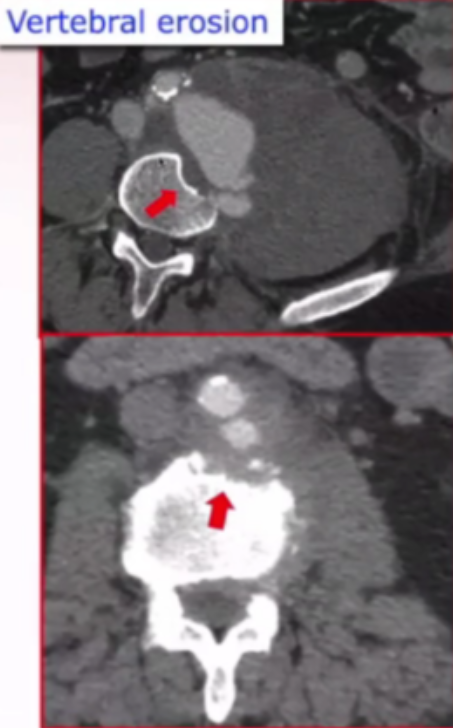

临床表现主动脉周围炎症97%、瘤体渗漏76%,部分患者合并椎体侵蚀、腔静脉血栓。

感染性主动脉瘤作为临床棘手病症,长期面临两大核心挑战:一方面是主动脉感染易失控或复发,细菌侵蚀主动脉壁后,传统药物治疗常难以遏制,进而可能发展为脓毒症;另一方面,感染导致主动脉壁结构薄弱,极易引发致命性的动脉瘤破裂。

研究团队引用文献(Yu S Yetal ,J Vasc Surg 2012)指出,此类患者死亡原因中,动脉瘤破裂占比高于脓毒症,且临床中药物治疗失败案例屡见不鲜——有患者经19天药物治疗后,动脉瘤直径从6.5cm增至8.5cm,另有患者3天内瘤体从62×67mm扩大至68×76mm,充分凸显单纯药物治疗难以阻断病情进展的困境。